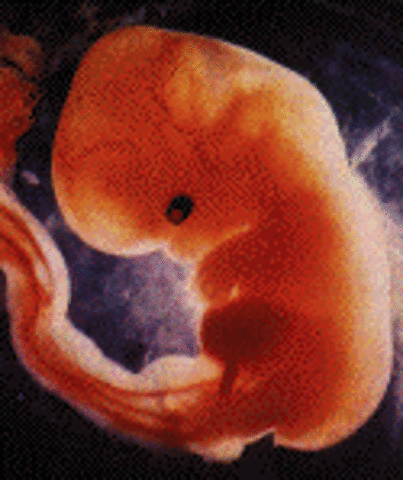

Embryo becomes 1/4 inch, spinal cord begins to close, first blood cells and blood vessels develop, heart is formed and begins beating, brain develops into 5 parts, optic cavaties and appendage cells are in place to be developed.

• Week 7

Week 7

Embryo is now 1/2 inch, heart beats with 1 chamber, arms and legs begin to grow, jaw and vocal cords begin forming the lungs, the liver, the pancreas, and the thyroid gland begin forming.